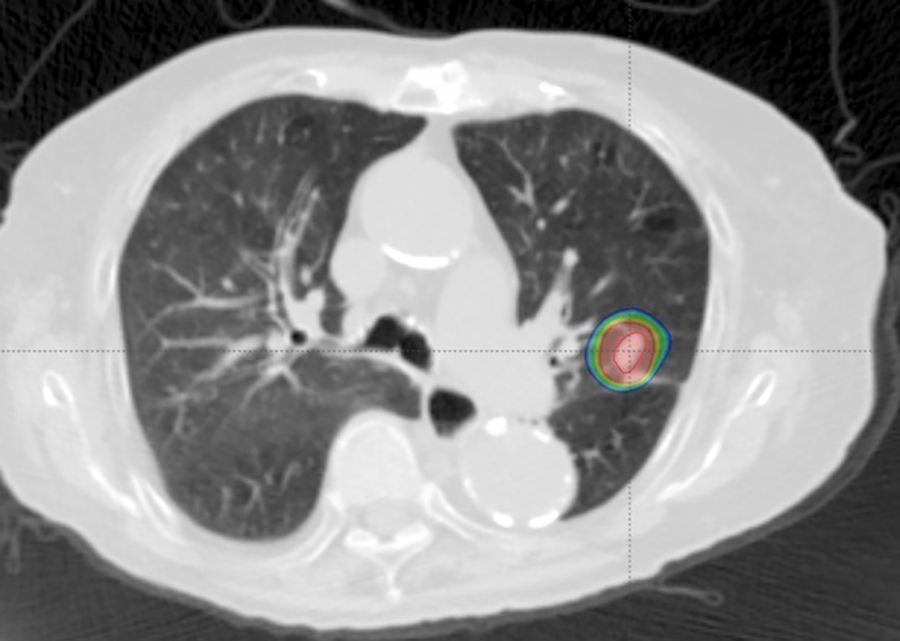

体幹部定位放射線治療:SBRT(Stereotactic Body Radiation Therapy)

ミリ単位の高い精度で病巣に対して多方向から放射線を集中投与する方法です。一般に1~2週間など短い期間で高線量を処方し、効果が期待される治療法です。

肺や肝臓、脳、骨、小数個の転移などが主な対象になり、以前よりも広く用いられています。